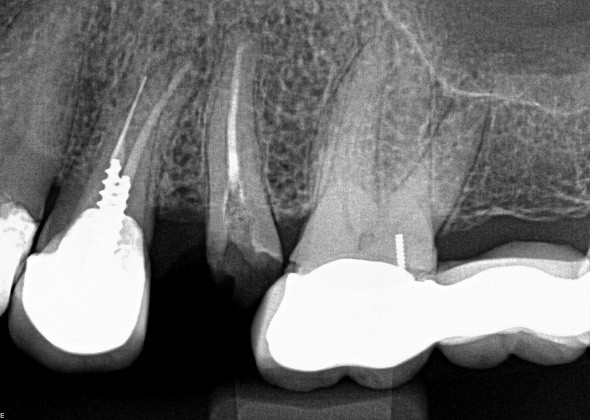

1.  (Select ONE OR MORE correct answers)

What observation(s) can be made for tooth 3.4?